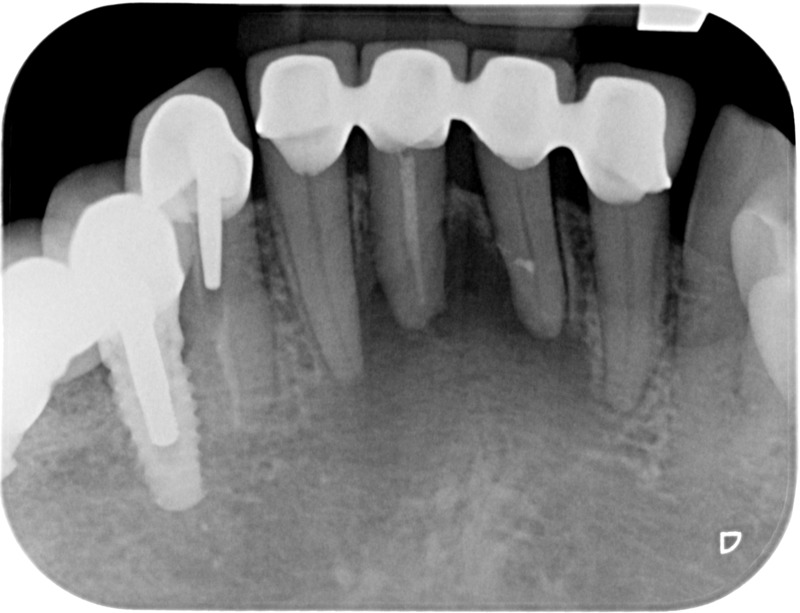

Après

• Reprise de traitement endodontique : La manœuvre consiste à retourner à l’intérieur des racines d’une dent déjà traitée. Il arrive occasionnellement qu’une nouvelle inflammation se déclare suite à une reprise de carie ou une fracture de la dent, ou si le premier traitement endodontique est incomplet. Après s’être assuré que la dent lésée était conservable, il convient de désinfecter de nouveau le réseau canalaire parfois très complexe. La nouvelle obturation des canaux devra être protégée aussi rapidement que possible pour éviter une éventuelle contamination bactérienne.